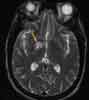

One week later, a second MRIscan shows a similar pattern of rightsidedlesions (Figure 3). No newlesions are detected. An area of increasedsignal intensity in the rightbasal ganglia is compatible with adiagnosis of septic embolism orinfarction.

On the 10th hospital day, the patientis transferred to the rehabilitationdepartment for gait training andspeech therapy. The antibiotic regimenis discontinued after 42 days, atwhich time the blood culture showsno bacterial growth. The patient's neurologicdeficits are steadily abating.